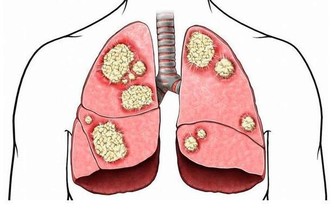

6、清除肺內毒素

人們每天除了會呼吸氧氣之外,還會吸過多的灰塵及細菌進入人的肺部,長期之後肺部會有諸多的毒素,毒素不但危害人體的健康,而且還會加速衰老,這時清除肺毒是有必要的。